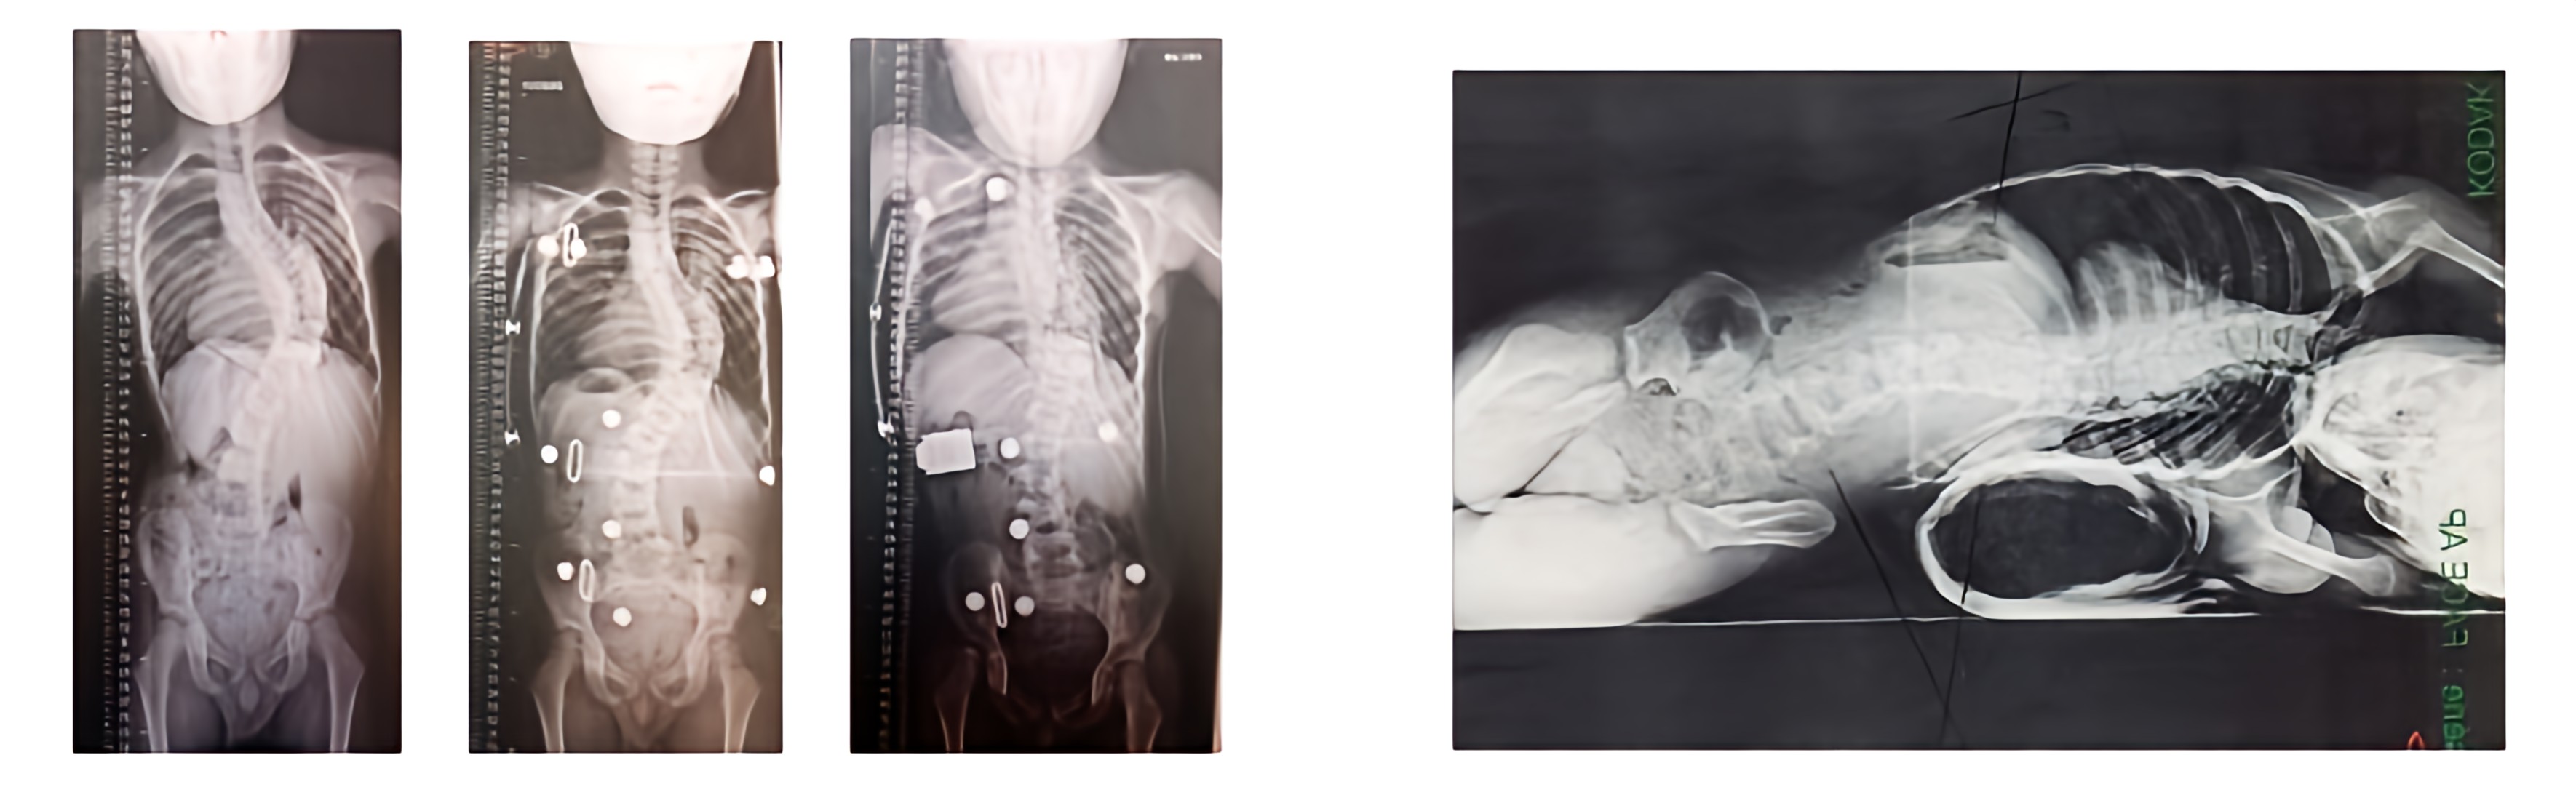

Limits of conservative orthopédic treatment : for example here, very little internal effect (Ehlers – Danlos syndrome)